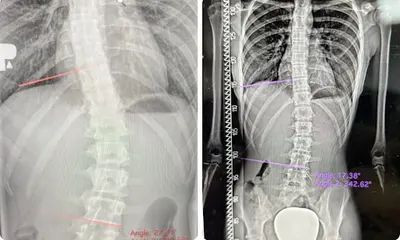

Centrum Chorób Kręgosłupa Łukasza Stolińskiego w Skierniewicach to miejsce specjalizujące się w rehabilitacji i leczeniu schorzeń kręgosłupa, w tym skoliozy i wad postawy. Położone przy Alei Niepodległości 4, placówka cieszy się doskonałą opinią pacjentów – średnia ocena na Google wynosi 5.0/5 na podstawie 65 recenzji. Pacjenci chwalą dokładne badania, szczegółowe wywiady i indywidualnie dobierane ćwiczenia, które pomagają w codziennej poprawie kondycji. Dr Łukasz Stoliński wyróżnia się zaangażowaniem i spokojnym podejściem, szczególnie do dzieci i młodzieży. Wizyty często trwają ponad dwie godziny, co pozwala na omówienie historii leczenia, wyników badań i planu terapii. Rodzice podkreślają, że lekarz cierpliwie odpowiada na pytania, motywuje młodych pacjentów do ćwiczeń i utrzymuje kontakt między wizytami, np. poprzez SMS. Dzięki temu wielu zgłasza realne efekty, jak brak bólu czy stabilizacja wady. W Skierniewicach centrum stało się wyborem dla osób szukających rzetelnej opieki ortopedycznej i rehabilitacyjnej. Pacjenci doceniają empatię i wiedzę specjalisty, co buduje poczucie bezpieczeństwa i zaufania. To miejsce warte polecenia dla tych, którzy zmagają się z problemami kręgosłupa. (198 słów)